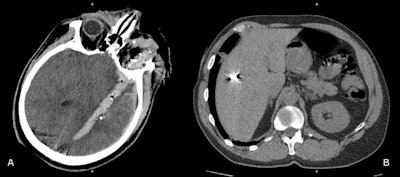

War injuries like these four cases are encountered on a daily basis at Zaporizhia Regional Hospital. (A) Penetrating gunshot wound. The wound channel passes through the left orbit and the left hemisphere of the brain, containing blood, air bubbles. and metal debris. (B) Shrapnel wound of the liver. (C) Gunshot wound of left hemithorax. The wound channel passes through the left lung with contusion of perifocal parenchyma, left pneumothorax, mediastinal and left subcutaneous and intramuscular emphysema. (D) Gunshot wound of left orbit and left maxillary sinus with multiple metal pellets and hemosinus. Images courtesy of Dr. Andrii Makarenkov.The department's equipment includes a Toshiba Activion16 CT scanner and a stationary angiographic C-arm Toshiba INFX-8000V machine. Medical staff usually continue working during air raids and rocket attack sirens. Sometimes the electricity is cut during CT scans. Contrast media and other consumables are in sufficient quantity for the moment, he noted.